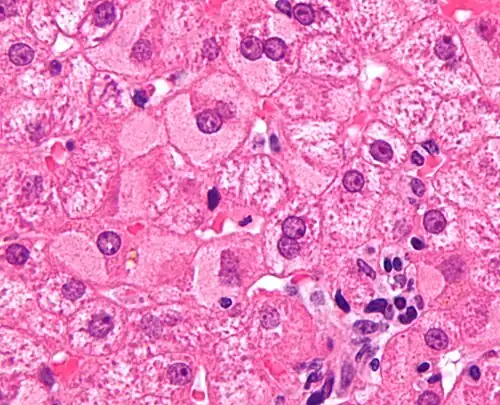

Ground glass hepatocytes -